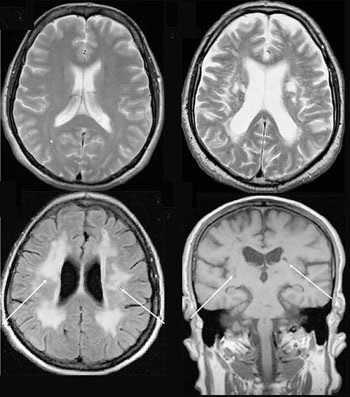

МР-заключение о наличии опухоли вилочковой железы обычно базируется на локальном увеличении железы, выявлении связи опухоли переднего средостения с железой. Интенсивность сигнала от опухоли чаще выше, чем от нормальной ткани железы. Большинство инкапсулированных опухолей дают гомогенный сигнал как на Т1, так и на Т2-изображениях. Инвазивные опухоли чаще негомогенные на Т2-зависимых изображениях.

Хорошая визуализация сосудов при МРТ с синхронизацией позволяет выявлять нечеткость их контуров при инвазии опухолью. Перикард на ЭКГ-синхронизированных изображениях выглядит как тонкая линия, низкой интенсивности толщиной менее 4 мм. При его инвазии возможно выявление прерывистости этой линии с замещением ее высокоинтенсивной опухолевой массой.

Кисты вилочковой железы обладают низкой интенсивностью сигнала на T1-зависимых изображениях и высокой на Т2-зависимых. Спонтанное кровотечение в кисту приводит к повышению сигнала на Т1-зависимых изображениях в связи с парамагнитным эффектом метгемоглобина.